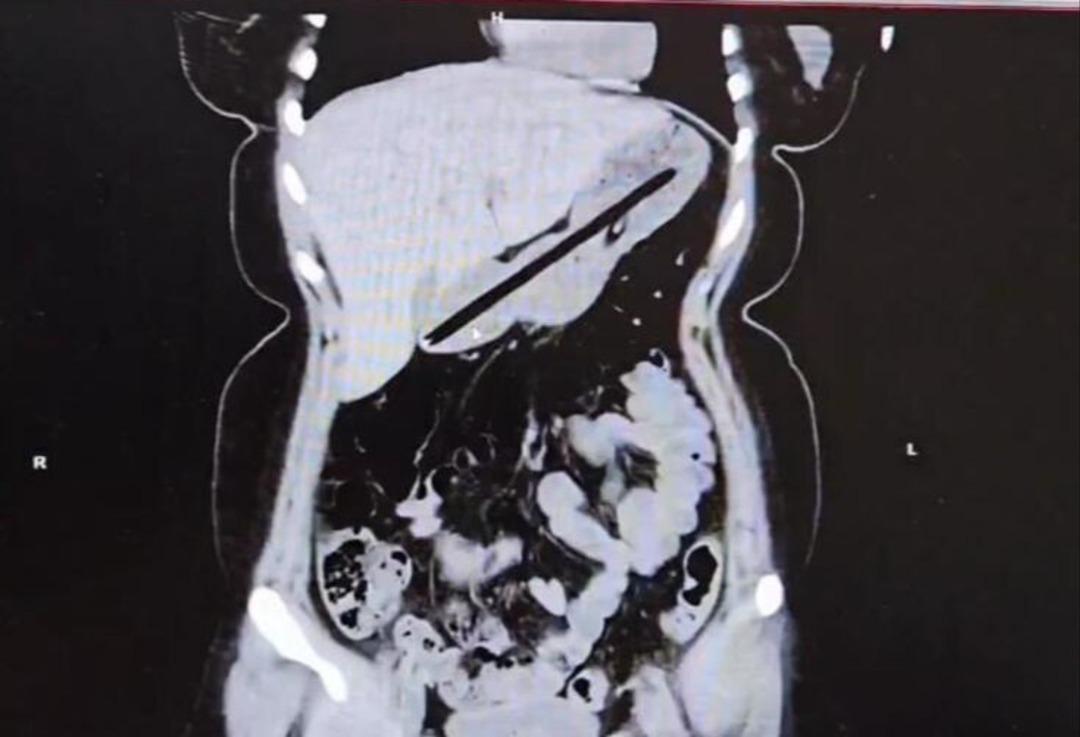

Ağrı'da Obsesif Kompulsif Bozukluk (OKB) rahatsızlığı bulunan 22 yaşındaki kadın, kalem yutma şikayetiyle hastaneye kaldırıldı. Ailesi tarafından Ağrı Eğitim ve Araştırma Hastanesi Acil Servisi'ne getirilen hastanın midesinde yabancı cisim tespit edildi.

Operasyonu gerçekleştiren Dr. Öğretim Üyesi Adem Aslan, ilk kez böyle bir vakayla karşılaştıklarını belirterek, "22 yaşındaki bayan hastamız kalem yutma şikayetiyle ilçe devlet hastanemize başvurmuştu. Tomografisinde midesinde yabancı cisim olduğu görüldü. Biz de tetkiklerimizde midesinde kalem olduğunu gözlemledik. Daha önce toplu iğne, kemik parçası gibi yabancı cisimlerle karşılaşıyorduk ama bu kadar uzun ve ince bir cisim ilk kez karşımıza çıktı. Midenin boşalması için bir gün bekledik ve ertesi gün yaptığımız endoskopide hastanın bir değil iki kalem yuttuğunu gördük." ifadelerinde bulundu.